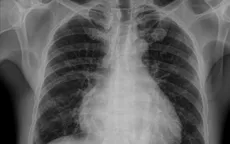

tổn thương phổi

Tổn thương phổi - nguyên nhân hàng đầu gây tử vong liên quan truyền máu